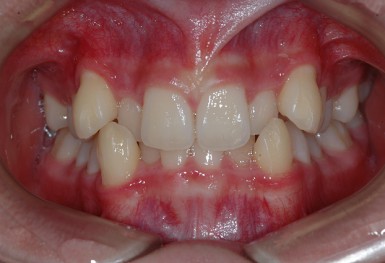

심한 덧니